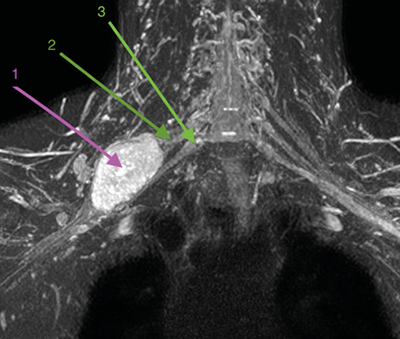

Con la orientación diagnóstica inicial de schwannoma de plexo braquial derecho con escasa repercusión clínica, se decidió actitud expectante. Se instauró tratamiento analgésico de primer escalón y ansiólisis a demanda para dormir. El paciente era reticente al tratamiento neuromodulador debido a sus efectos secundarios. Seis meses después, tras una nueva RM de control, se observó un discreto crecimiento de la lesión con probable efecto compresivo por los músculos escalenos anterior y medio (Figuras 1 y 2). Se indicó una infiltración diagnóstico-terapéutica con toxina botulínica tipo A (Botox®) ecodirigida. Las crisis de dolor eran más frecuentes y de más minutos de duración y empezaban a afectar su calidad de vida. EVA 2-3 en reposo, 8-9/10 en las crisis.

Fig. 2. RM coronal en STIR. 1. Schwannoma de plexo braquial derecho. 2. Tronco medio del plexo braquial. 3. Tronco inferior del plexo braquial